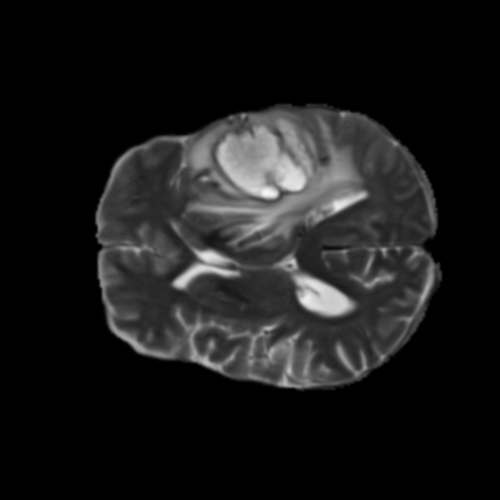

Ejemplos de Modalidades MRI

Visualización de las 4 modalidades de resonancia magnética y las segmentaciones de zonas tumorales utilizadas para entrenar el modelo

Glioma de Alto Grado (HGG)

FLAIR HGG

FLAIR

T1ce HGG

T1ce

T2 HGG

T2

T1 HGG

T1